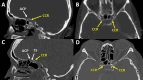

Background The middle clinoid process (MCP), particularly caroticoclinoid ring (CCR) type of the MCP, is an important part of the sphenoid bone for skull base surgery. Previous studies have shown a wide range of MCP prevalence affected by various factors. However, no study has investigated the association between the MCP and the presence of sellar lesions. Objectives The main aim of this study was to evaluate the prevalence of the MCP in the Thai population and factors associated with its presence. Materials and Methods We conducted a cross-sectional study on 400 sides from 200 patients (100 with and 100 without sellar lesions) using cranial computerized tomography scans. Demographic data and MCP characteristics were collected. The association between individual variables and the presence of the MCP was determined by univariate and multivariate analysis. Results The MCP was identified in 168 of 400 sides (42%). Patients with sellar lesions had a significantly lower prevalence of the MCP compared with normal controls (29.5% versus 54.5%, p < 0.001). Of all MCP only 6% were the CCR type. Univariate and multivariate analysis showed that the absence of the sellar lesion was the only factor significantly associated with presence of the MCP (odds ratio: 2.86; 95% confidence interval: 1.90-4.32; p < 0.001). Conclusion The prevalence of the MCP was relatively high in the Thai population, while the prevalence of the CCR was relatively low compared with previous studies. The absence of sellar lesions was the only factor associated with the presence of the MCP.